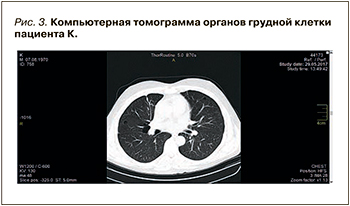

При проведении спирографии выявлены умеренные обструктивно-рестриктивные изменения; умеренное снижение жизненной емкости легких. На компьютерной томограмме органов грудной клетки обнаружены признаки буллезной эмфиземы, адгезивного плеврита, фиброзируюшего альвеолита (рис. 3).